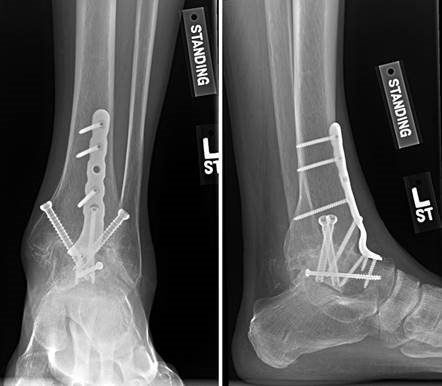

First MTP Arthrodesis

In cases of end-stage hallux rigidus, first MTP arthrodesis yields excellent, predictable outcomes. A dorsal longitudinal incision is made just medial to the EHL tendon. The joint is exposed, and aggressive cheilectomy is performed to remove all dorsal, medial, and lateral osteophytes. The remaining articular cartilage on the metatarsal head and the base of the proximal phalanx is resected using cup-and-cone reamers, which allow for infinite adjustment of the joint position prior to fixation.

Positioning of the fusion is the most critical step of the operation. The hallux must be positioned in 10-15 degrees of valgus, 15-20 degrees of dorsiflexion relative to the first metatarsal, and neutral rotation. Excessive dorsiflexion causes shoe impingement, while insufficient dorsiflexion leads to vaulting during gait and interphalangeal joint arthritis. Fixation is most reliably achieved using a pre-contoured dorsal locking plate combined with a lag screw crossing the fusion interface.

Image